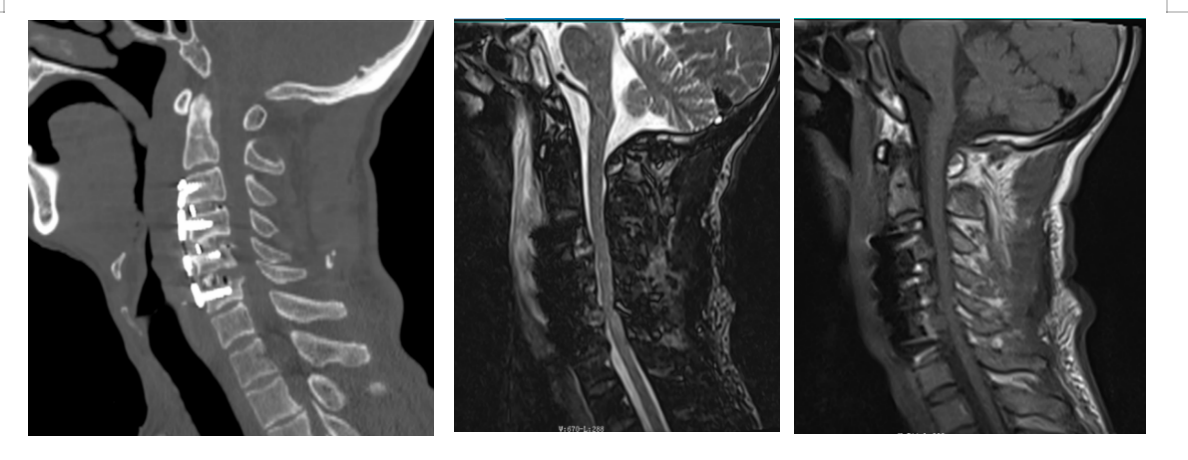

大众卫生报·新湖南客户端3月9日讯(通讯员 匡登峰 申宽宏)近日,祁东县人民医院脊柱外科团队再传捷报。在衡阳市中心医院派驻专家申宽宏副主任医师的带领下,团队成功为2名颈脊髓损伤患者实施了“内镜辅助下颈椎前路减压融合内固定术”。术后患者神经功能恢复良好,疼痛症状显著缓解,康复进程远超预期,赢得了患者及家属的高度赞誉。

医疗团队在镜下精准完成了椎间盘/髓核摘除、椎管减压等核心步骤,彻底解除了脊髓与神经的压迫。随后,通过微小切口精准植入融合器与内固定装置,有效重建了脊柱的生理曲度与力学平衡。

相较于传统开放手术,该术式具有创伤小、出血少、疼痛轻、恢复快的显著优势。术中实现了对脊髓的“零侵袭”,极大降低了手术风险,为患者的快速康复奠定了坚实基础。

此次内镜辅助下颈椎前路手术的成功开展,不仅是脊柱内镜微创技术的又一次突破,更是衡阳市中心医院优质医疗资源下沉、紧密型医联体建设成果的生动体现。

自衡阳市中心医院脊柱外科专家申宽宏副主任医师入驻祁东以来,祁东县人民医院脊柱外科团队秉持“以患者为中心”的服务理念,深耕微创技术领域,持续加强学科建设。通过“传帮带”的协作模式,团队先后攻克多项脊柱微创诊疗难题,逐步实现了对脊柱全节段、多类型疾病的微创化治疗。